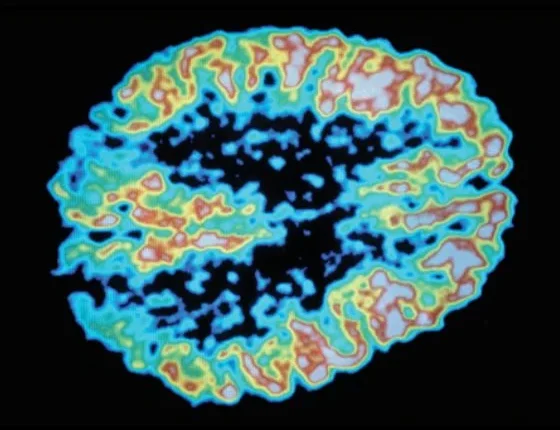

Πώς συνδέονται ο μεταβολισμός και η δραστηριότητα του εγκεφάλου

Υπάρχει άμεση σχέση μεταξύ του μεταβολισμού στα κύτταρα του εγκεφάλου και την ικανότητά τους να επισημάνουν πληροφορίες, αναφέρει νέα μελέτη του Πανεπιστημίου McGill και του Πανεπιστημίου της Ζυρίχης.

Τα ευρήματα που δημοσιεύονται στο περιοδικό Nature Communications, αποκαλύπτουν ότι ο μεταβολισμός ελέγχει τις διαδικασίες που αναστέλλουν τη δραστηριότητα του εγκεφάλου, όπως αυτές που εμπλέκονται σε σπασμούς. Η μελέτη αποκαλύπτει ένα σύνδεσμο μεταξύ του πώς τα κύτταρα του εγκεφάλου παράγουν ενέργεια και πώς τα ίδια κύτταρα σηματοδοτούν πληροφορίες, διαδικασίες που οι νευροεπιστήμονες συχνά θεωρούν πως είναι διαφορετικές και γίνονται ξεχωριστά.

Τα πειράματα έδειξαν μια απροσδόκητη σχέση μεταξύ του πώς τα μιτοχόνδρια των κυττάρων του εγκεφάλου παράγουν ενέργεια και πώς τα ίδια κύτταρα παρέχουν πληροφορίες σήματος. Τα κύτταρα του εγκεφάλου ζευγαρώνουν αυτές τις δύο ανεξάρτητες λειτουργίες με τη χρήση μικρών χημικών αγγελιοφόρων που ονομάζονται αντιδραστικά είδη οξυγόνου (ROS), τα οποία συνδέονται συνήθως με τη σηματοδότηση του κυτταρικού θανάτου. Ενώ τα ROS είναι γνωστό πως έχουν ρόλο σε ασθένειες της γήρανσης του πληθυσμού, όπως οι νόσοι του Αλτσχάιμερ και του Πάρκινσον, η νέα μελέτη δείχνει ότι παίζουν επίσης σημαντικό ρόλο στον υγιή εγκέφαλο.